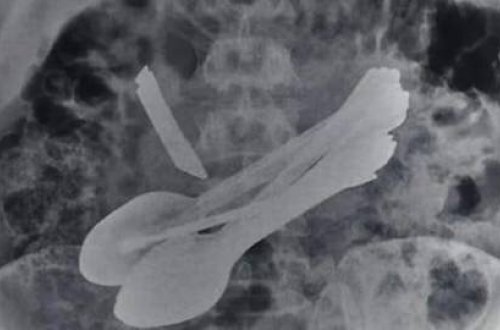

Belə şey nə görüldü, nə də eşidildi -

Mədəsindən elə şeylər çıxdı ki,...

adamın

qarnında

vintaçan

xəstə

olduğu

əməliyyat

qarnından

xəstəxanaya

fırçası

qaşıq

xəstənin

qapı

kilidi